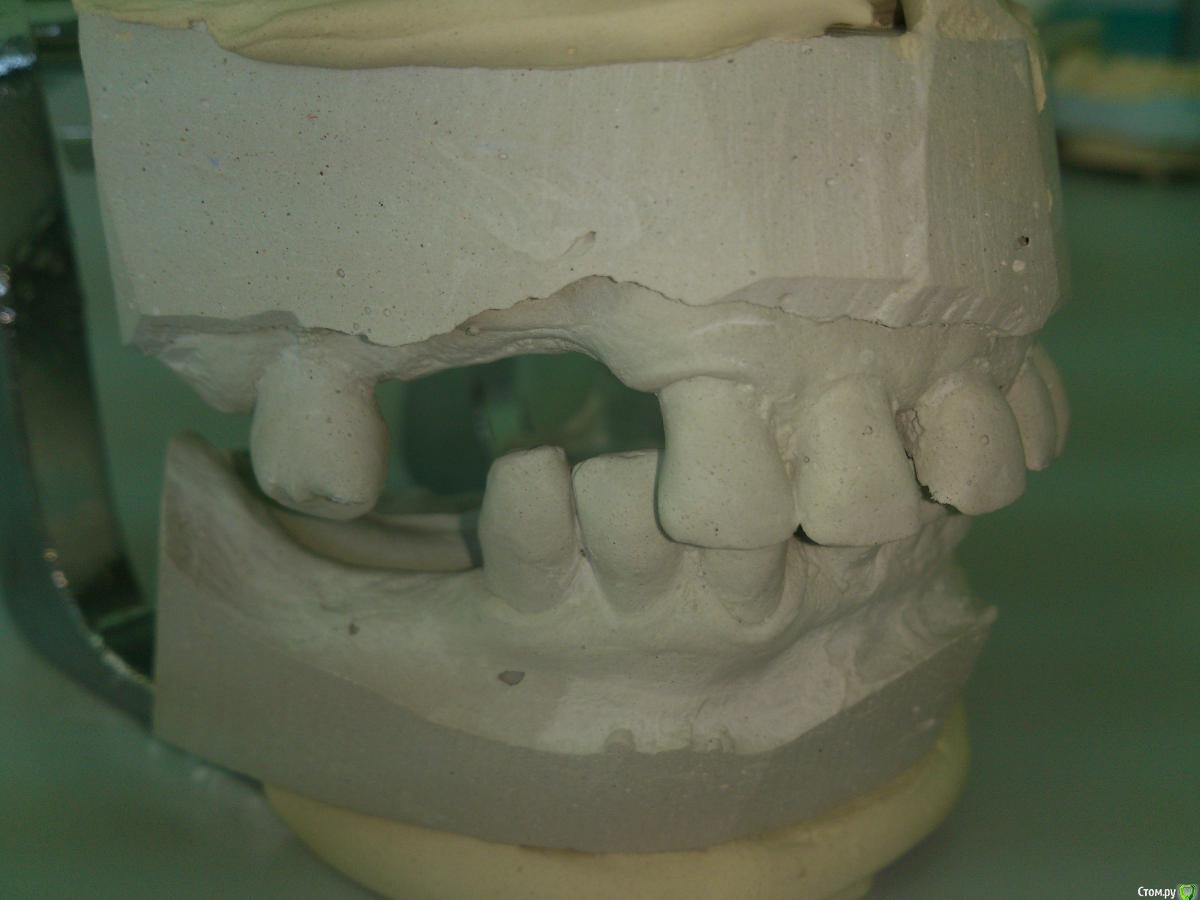

SanderS Опубликовано 16 июня, 2015 Поделиться Опубликовано 16 июня, 2015 Пациентка 1950 г.р. обратилась с жалобами на эстетику и затрудненное пережевывание пищи. 3.1, 4.1, 4.2, 3.7 удалили из-за подвижности , 2.2 так же ушел из-за подвижности и сильного выдвижения.Как быть? В планах: ВЧ - вкладки+МК мост+бюгель замки, НЧ - МК мост+бюгель замки. Сомневаюсь по поводу замков, может лучше опорно-удерживающие? Или вообще рассмотреть имплантацию, но хирург в отпуске, КТ заканчивают ремонт, а пациент просит завершить к концу июля. Ссылка на комментарий

Larnary Опубликовано 16 июня, 2015 Поделиться Опубликовано 16 июня, 2015 (изменено) Ну полноценный план лечения давать без элементарной панорамы не серьезно. А что закончить всю работу до конца июля,если речь идет о качестве-лично я бы попрощался с таким пациентом.почему так категорично,работа не простая и может быть немало подводных камней и загонять себя в узкие рамки опрометчиво. Но в любом случае пациенту сначала надо объяснить всю ситуацию и сказать,что для качественного лечения может потребоваться значительно больше времени,особенно,если договоритесь об имплантации.по-поводу замков,чую по моделям и причине удаления зубов,там беда с пародонтом,а потому замки не лучший способ восстановления.А вот,что лучше...ждем снимки Изменено 16 июня, 2015 пользователем Larnary 2 Ссылка на комментарий

Rumata Опубликовано 17 июня, 2015 Поделиться Опубликовано 17 июня, 2015 Учитывая состояние зубов, замки, на мой взгляд, рискованно. Либо вариант с более лабильным соединением. Ссылка на комментарий

SanderS Опубликовано 23 июня, 2015 Автор Поделиться Опубликовано 23 июня, 2015 пациент имплантаты не потянет, удалять естественно не хочет, значит будет ЧСПП, будет с ними копить на имплантацию. Ссылка на комментарий

krokomot Опубликовано 23 июня, 2015 Поделиться Опубликовано 23 июня, 2015 В таком случае оставил бы 2 клыка снизу, а остальное на выход + 2 съемника. Не хочет пусть тогда ищет помощь в другом месте, потому как в конечном итоге обвинит вас в своих проблемах. Ссылка на комментарий